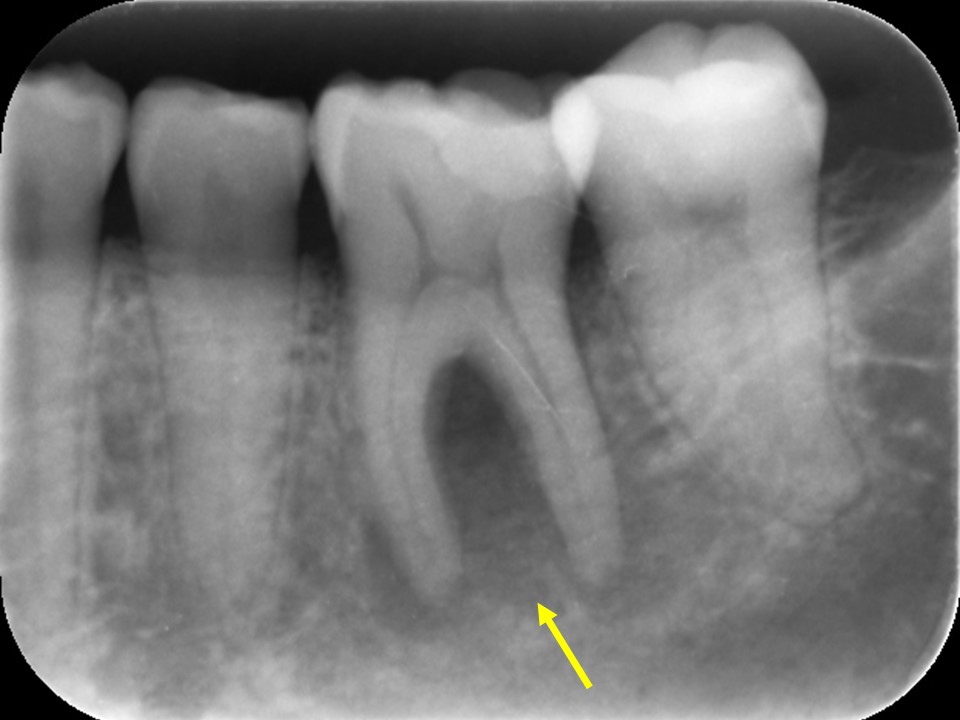

| 治療後レントゲン | 治療後CT |

|---|---|

| 治療後レントゲン |

|---|

| 治療後CT |

感染根管治療10か月後のレントゲンおよびCT画像です。

根尖病変は消失し、歯槽骨は完全な再生を認め治癒しています。